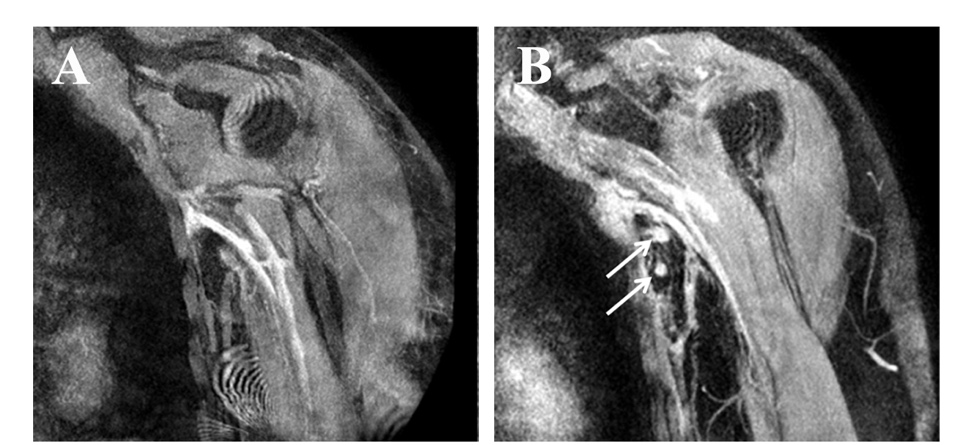

The researchers tracked the outcomes using magnetic resonance lymphangiography (MRL), an imaging technology that revealed significant improvement in lymphatic drainage and reduction in limb volume.

"Seeing the lymphatic pathways reform and begin functioning effectively within a year after the procedure was both unexpected and rewarding," remarks Jiang.